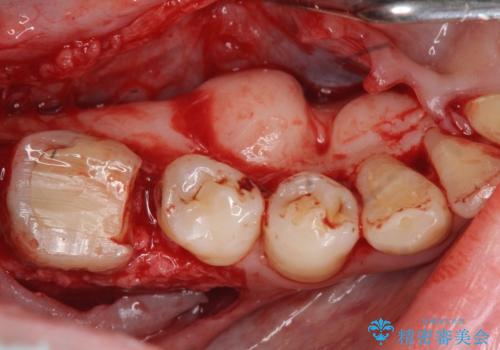

歯周外科を行うことで、歯ぐきの位置を下げ歯の高さを作り出し安定したクラウンの装着が可能となります。また同時に舌の邪魔となっていた骨隆起の除去を行うこととしました。

歯周外科に際しては、静脈内麻酔を行うことでほとんど記憶のないうちにリラックスした状態で受けていただくことができました。